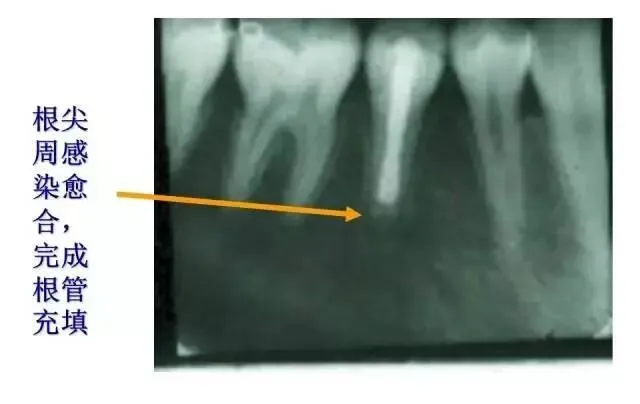

>PPT典藏 | 根尖诱导成型术